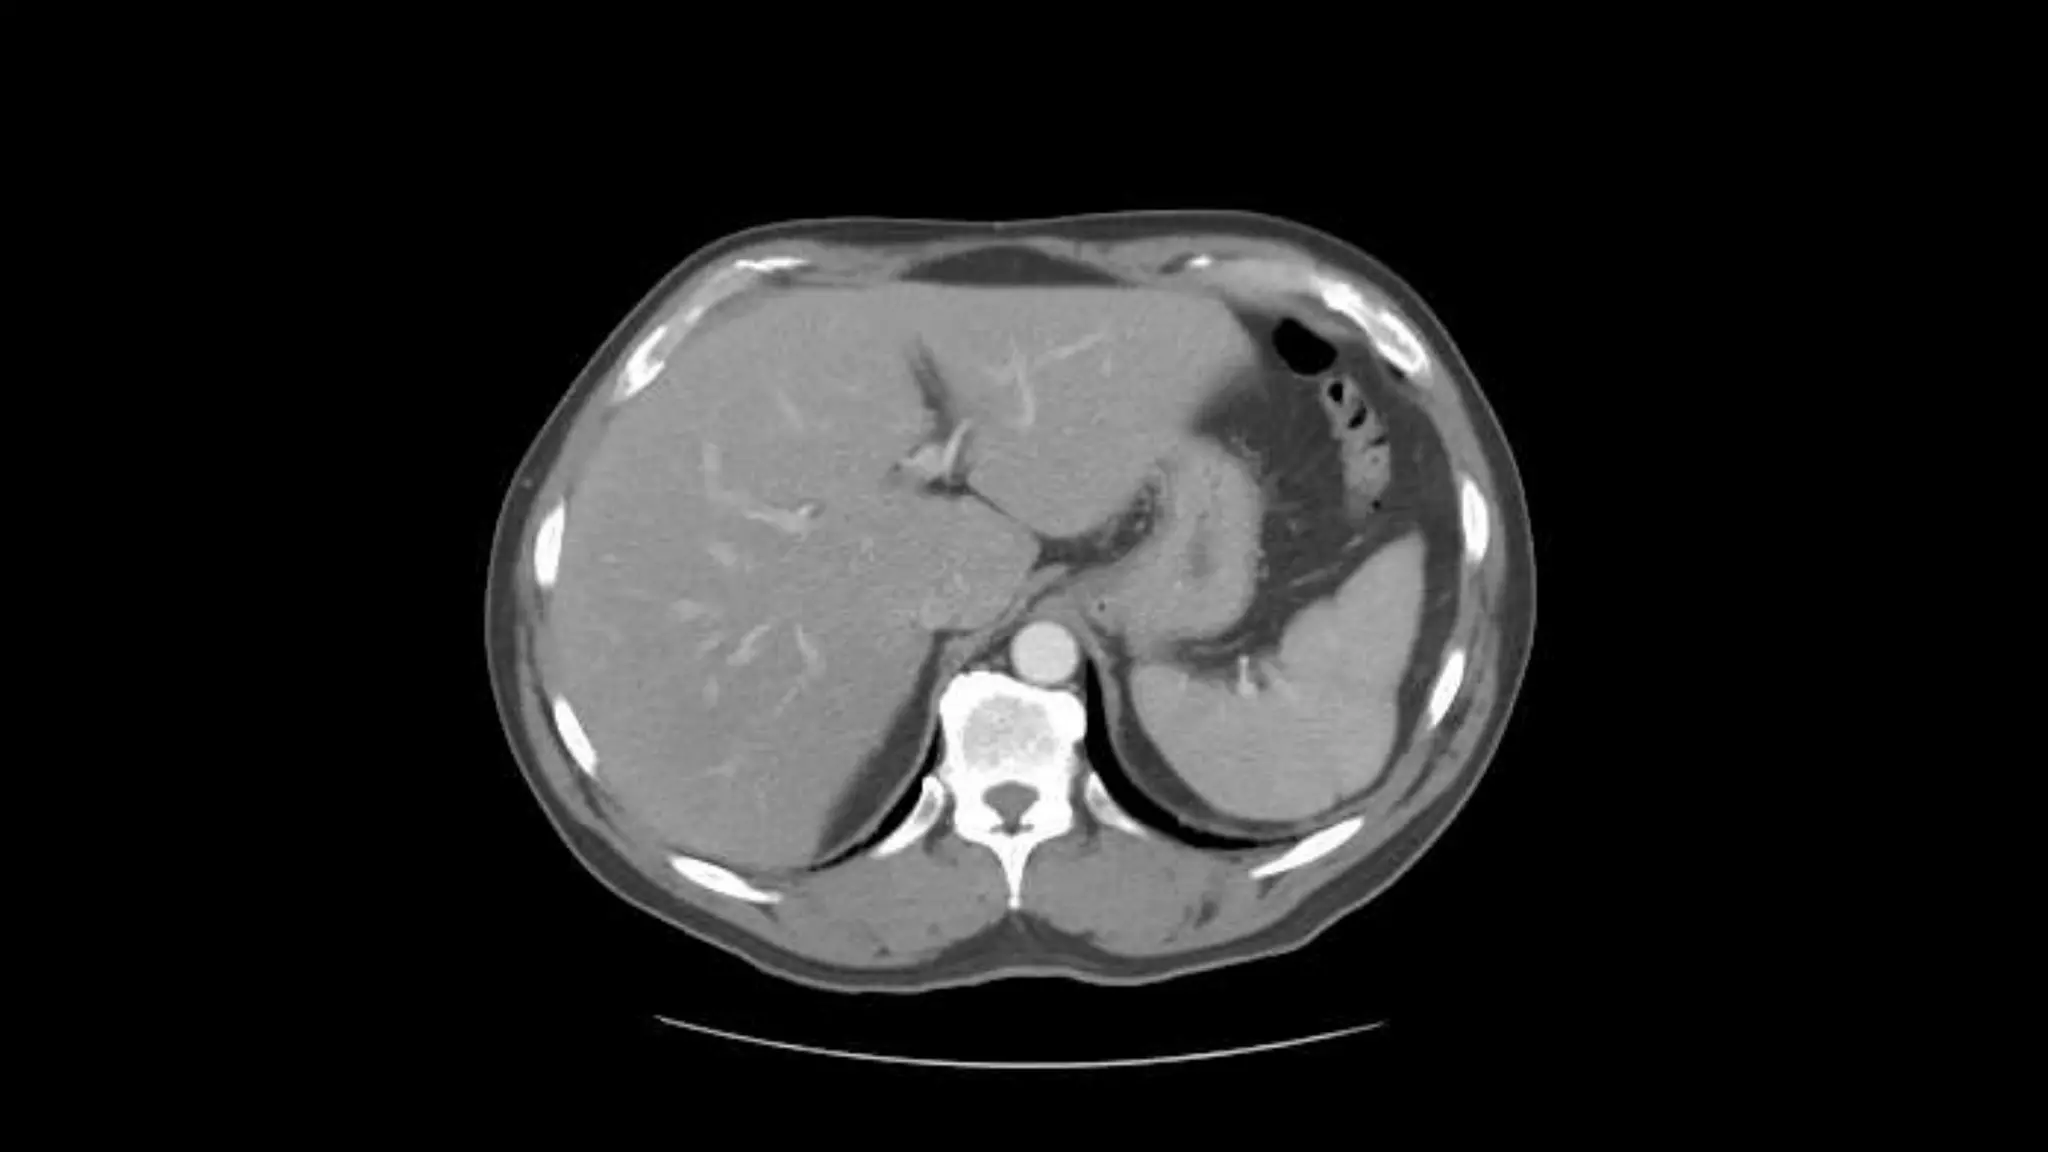

This is the Superior Mesenteric Artery branching

off the Aorta.

Rt. and Lt.Kidneys

Pancreas

Renal Veins emptying into the IVC. We also see the right renal artery branching

off the Aorta, follow it down till you see it enter the right kidney. The Superior

Mesenteric Vein is outlined on the top of this image. If you follow the SMV up, you

will see it empty into the Portal Vein.